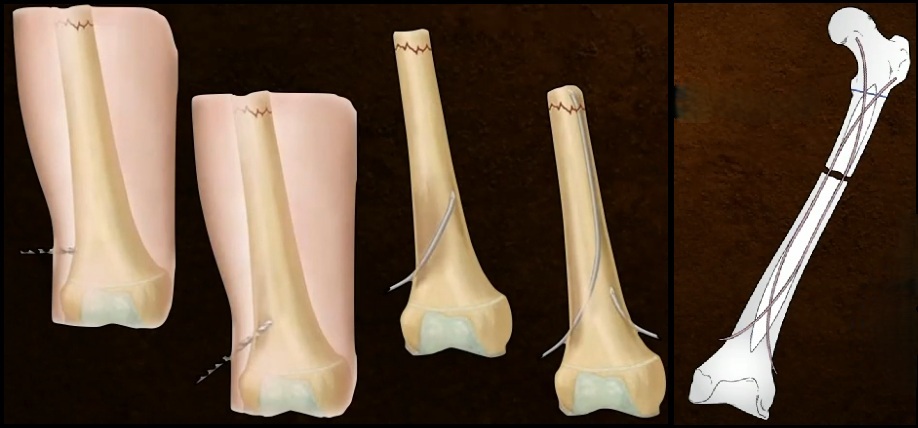

7

TTO 6 - 10 anos?

HASTES FLEXÍVEIS

Placa (>50 Kg)

Fixador Externo (Cominuição)

8

TTO > 10 anos?

HASTE RÍGIDA

Haste Flexível ( < 50 Kg)

Placa (Cominuição)

9

Detalhe Haste Flexível (2)

1. Ideal < 50 Kg e Padrões Estáveis de FX

2. Duas Hastes diâmetro 40% do diâmetro do ISTMO (80% do canal)